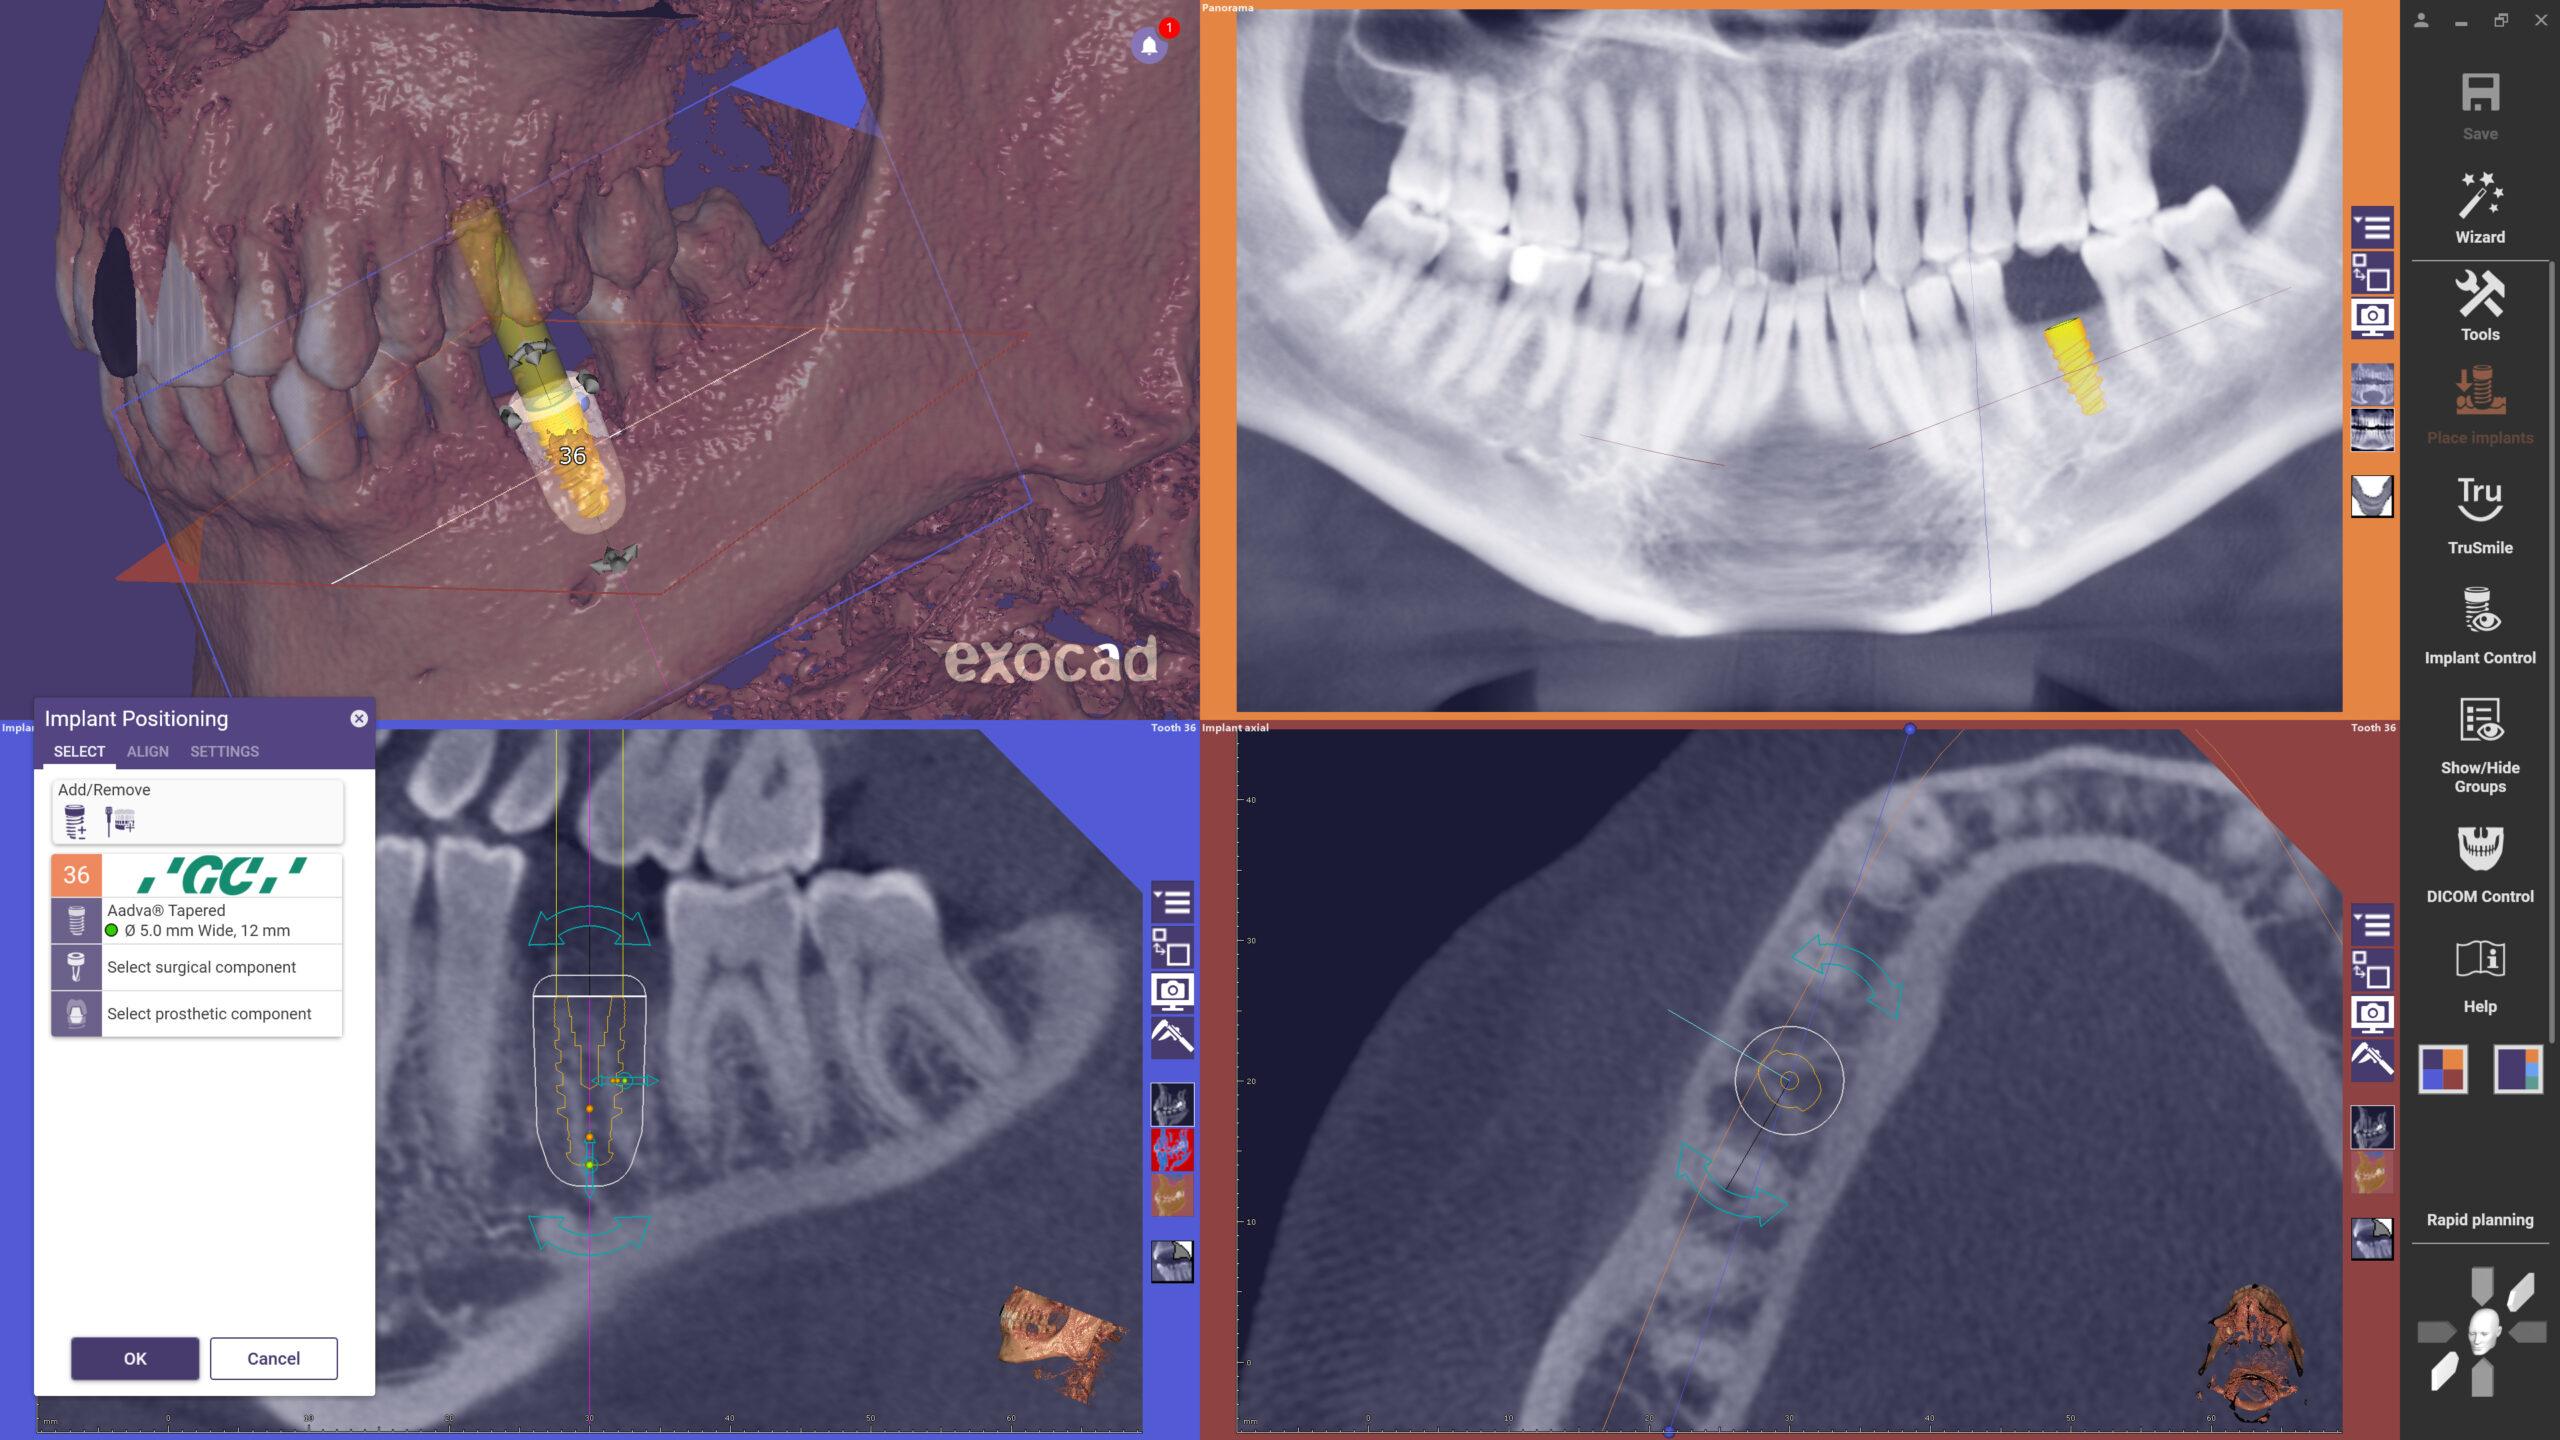

Exoplan je preoperativni softver koji se koristi za digitalno planiranje pozicije, veličine i orijentacije dentalnih implantata. Omogućava integraciju CBCT snimaka, intraoralnih i ekstraoralnih skenova, čime se dobija trodimenzionalni prikaz kosti, zuba i važnih anatomskih struktura. Na ovaj način, stomatolog dobija jasnu i realističnu sliku situacije prije same operacije.

- Preciznost i sigurnost – detaljna vizualizacija omogućava tačno pozicioniranje implantata, smanjujući rizik tokom zahvata.

- Planiranje i proizvodnja hirurških vodilica – uz modul Guide Creator, moguće je interno dizajnirati i 3D printati vodilice, što donosi značajnu uštedu vremena i troškova.

- Exoplan podržava najveći broj implantoloških sistema i omogućava neusporedivo slobodu u izboru materijala i tehnologija. Trenutna podrška je za više od 16.000 implantata u preko 1.300 biblioteka; sa širokim izborom vodilica, svrdla in pinova za sidrenje koji podržavaju više od 34.000 različitih protokola vođene kirurgije